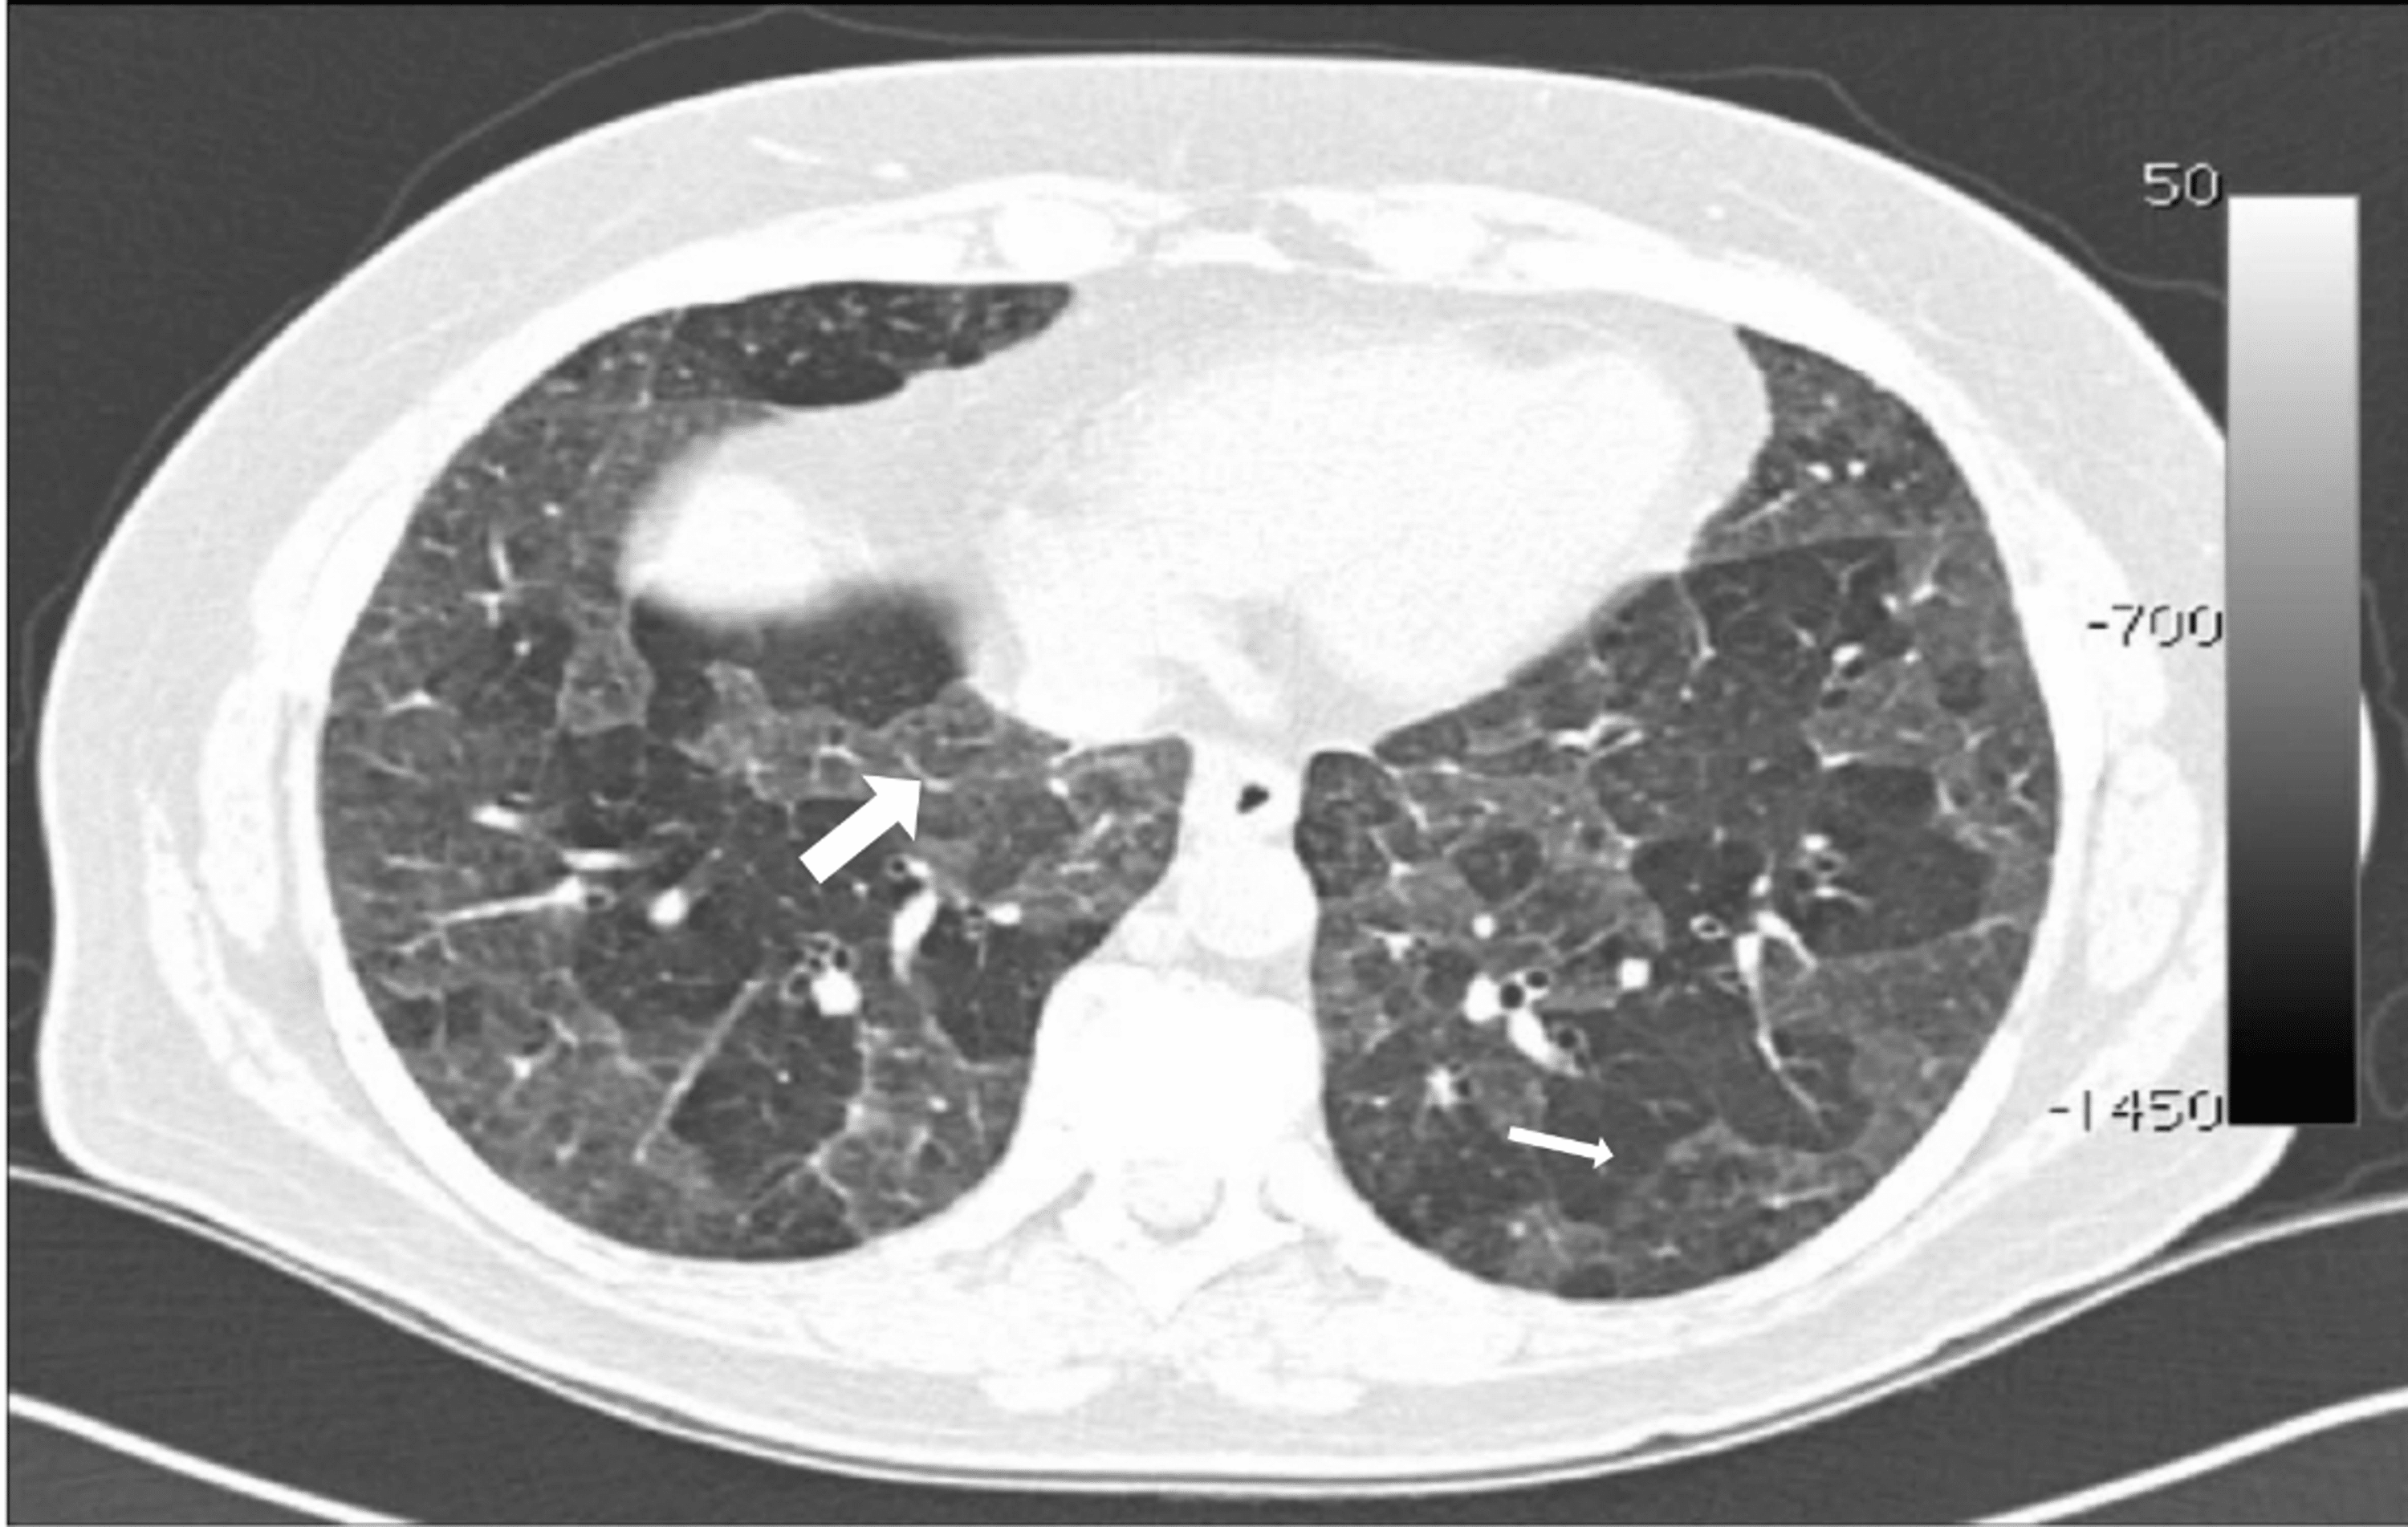

Challenges in pulmonary fibrosis · 1 Use of high resolution CT Smoking Associated Interstitial Lung Disease cigarette smoking is a recognized risk factor for development of interstitial lung disease (ild). Cigarette smoking is associated with a variety of pathologic conditions that affect the airways and. available evidence suggests most cases of desquamative. cigarette smoking is a risk factor for interstitial lung abnormalities (ilas) and interstitial lung diseases (ilds). smoking is also a. Smoking Associated Interstitial Lung Disease.

Changes in HRCT findings in patients with respiratory bronchiolitis Smoking Associated Interstitial Lung Disease available evidence suggests most cases of desquamative. cigarette smoking is a risk factor for interstitial lung abnormalities (ilas) and interstitial lung diseases (ilds). Cigarette smoking is associated with a variety of pathologic conditions that affect the airways and. smoking is also a risk factor for combined pulmonary fibrosis and. cigarette smoking is a recognized risk factor. Smoking Associated Interstitial Lung Disease.

Changes in HRCT findings in patients with respiratory bronchiolitis Smoking Associated Interstitial Lung Disease cigarette smoking is a recognized risk factor for development of interstitial lung disease (ild). cigarette smoking is a risk factor for interstitial lung abnormalities (ilas) and interstitial lung diseases (ilds). Cigarette smoking is associated with a variety of pathologic conditions that affect the airways and. smoking is also a risk factor for combined pulmonary fibrosis and. . Smoking Associated Interstitial Lung Disease.

Features of nonfi brotic smokingrelated interstitial lung disease Smoking Associated Interstitial Lung Disease cigarette smoking is a recognized risk factor for development of interstitial lung disease (ild). smoking is also a risk factor for combined pulmonary fibrosis and. cigarette smoking is a risk factor for interstitial lung abnormalities (ilas) and interstitial lung diseases (ilds). Cigarette smoking is associated with a variety of pathologic conditions that affect the airways and. . Smoking Associated Interstitial Lung Disease.